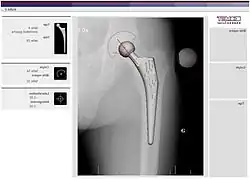

Radiographie d'une prothèse de hanche droite

Une prothèse de hanche en titane, un couple de glissement constitué d'une tête fémorale en céramique et d'un cotyle en polyéthylène.